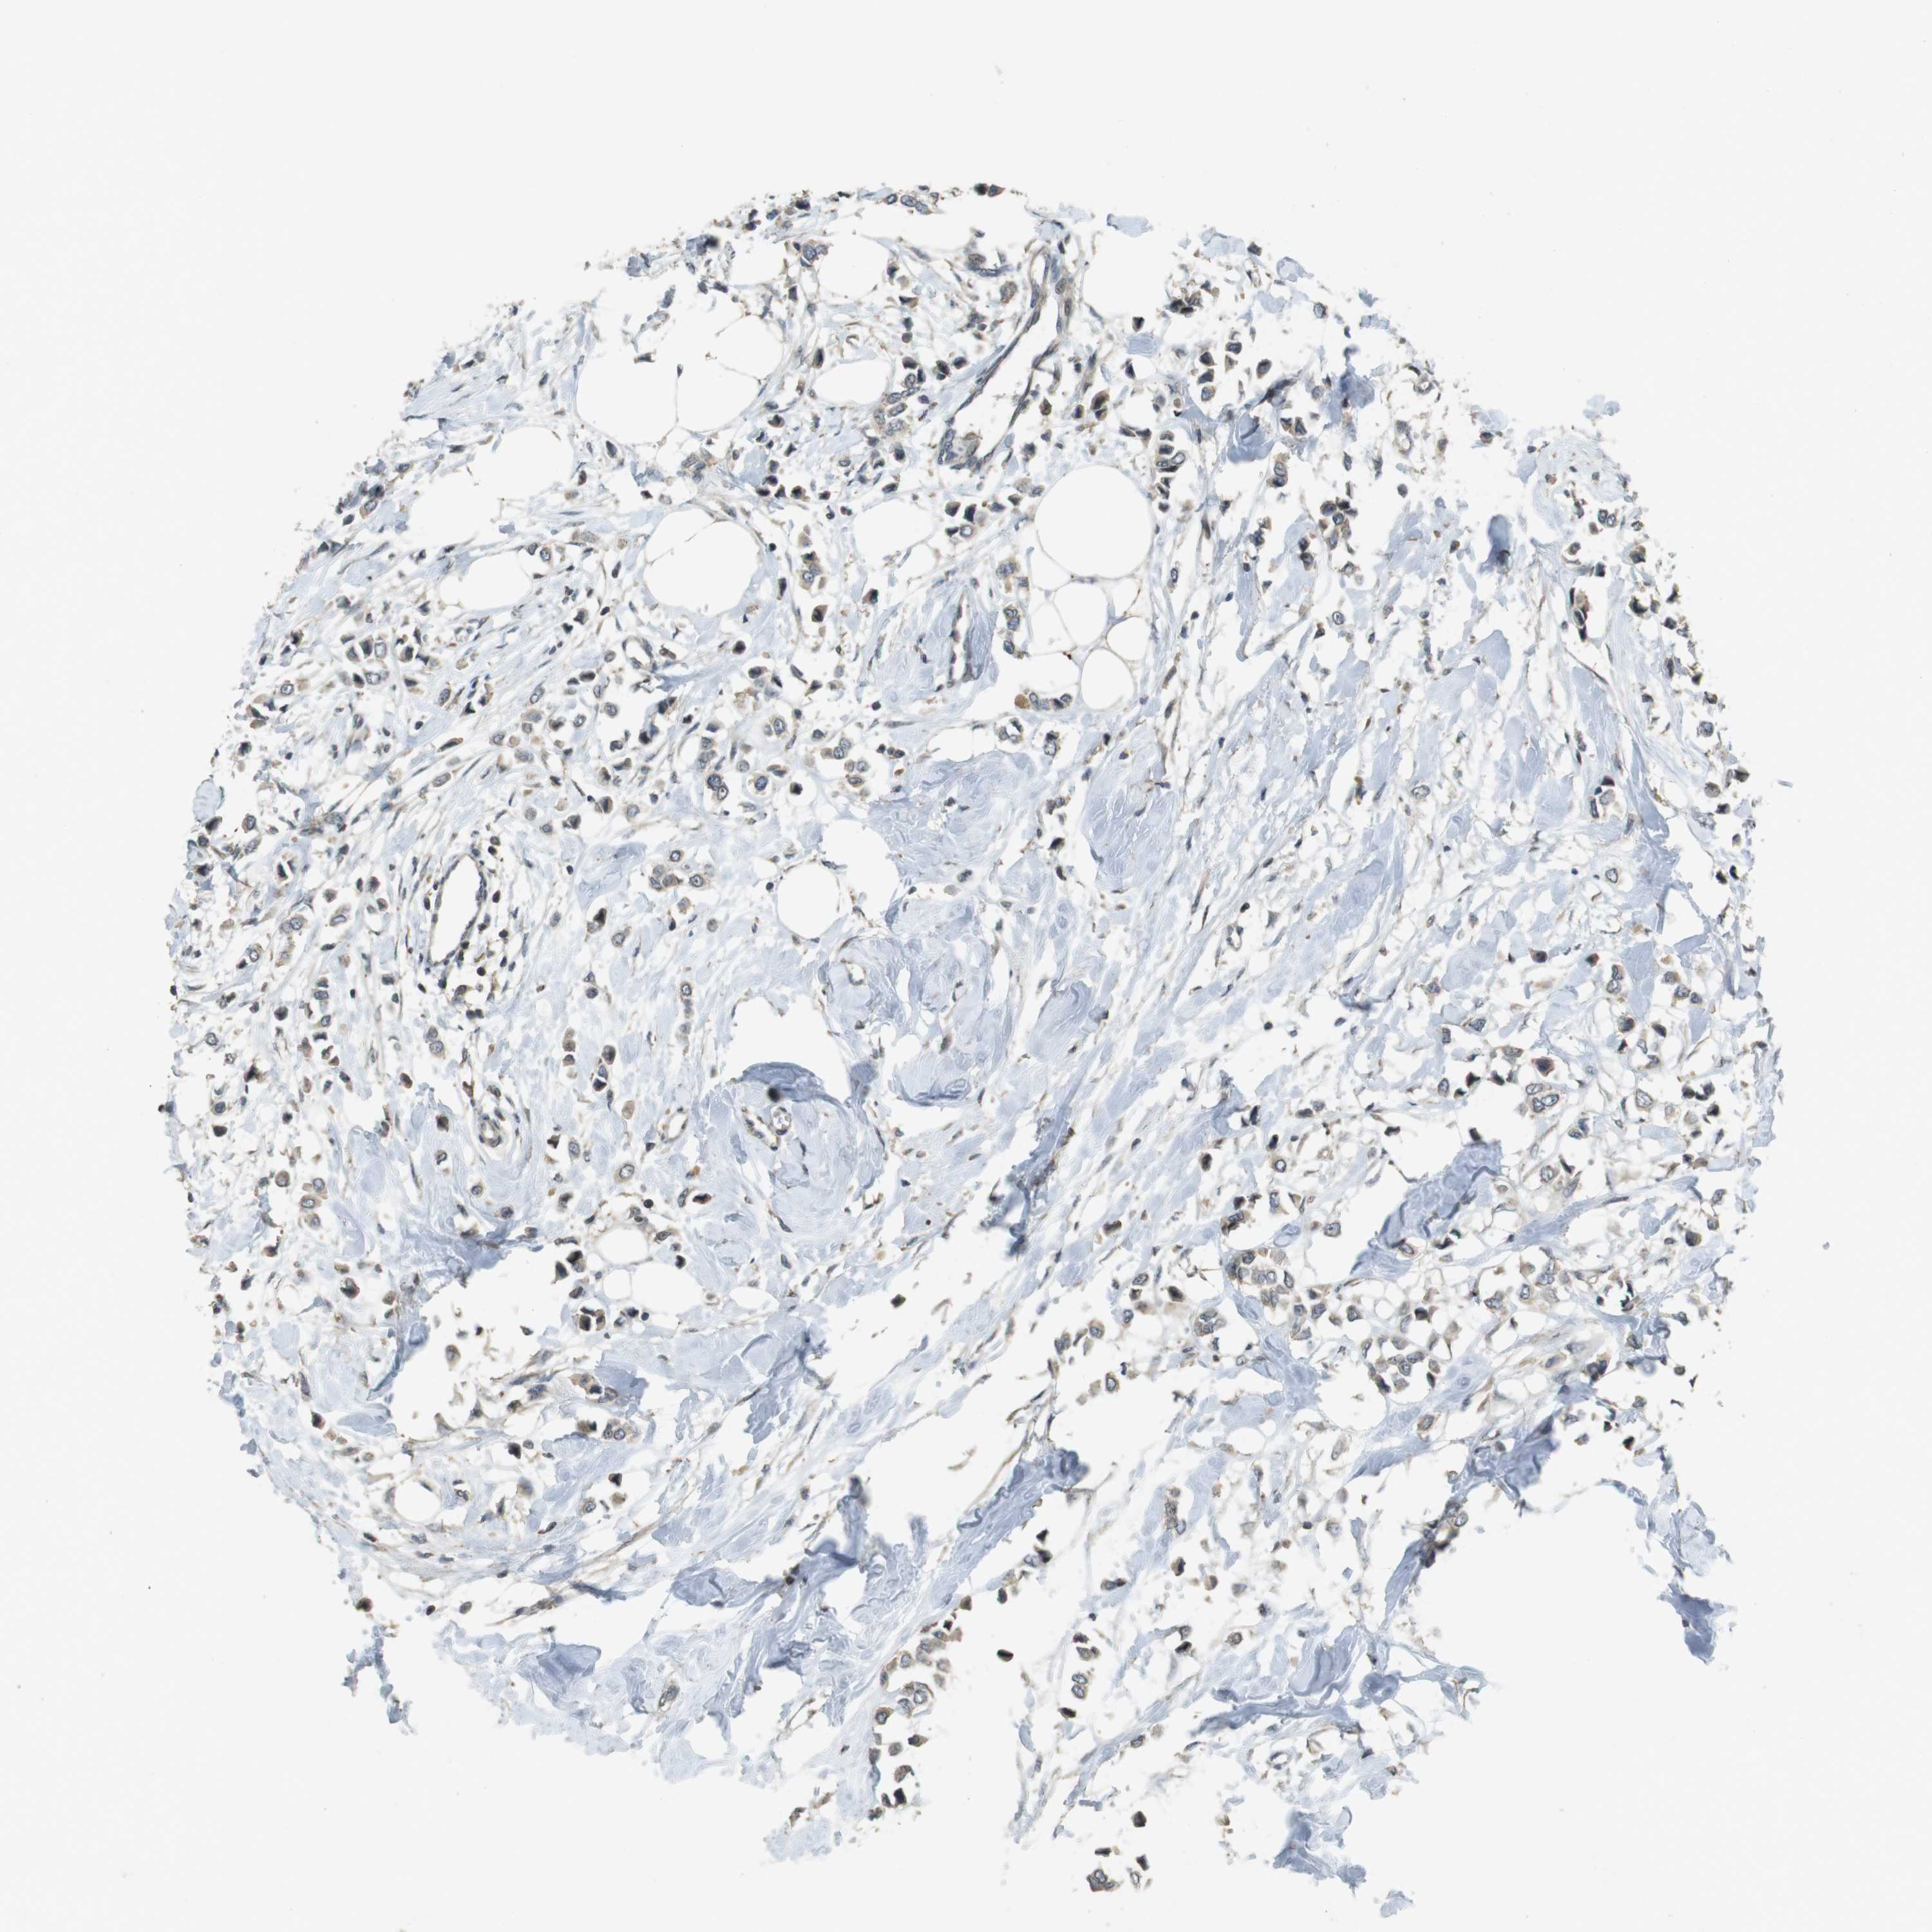

BRCA TCGA BRCA VALIDATION PROTEIN EXPRESSION

Breast cancer

Human cancer